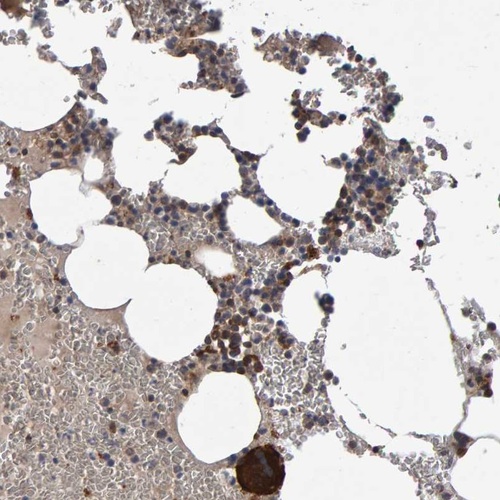

Immunohistochemical staining of human bone marrow shows cytoplasmic positivity in hematopoietic cells.